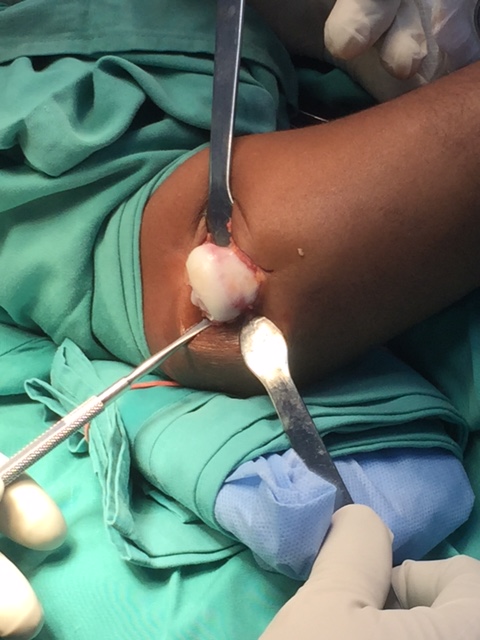

The pediatric orthopedic surgeon felt that excison of the radial head for the treatment of his dislocating radial head was Diego’s best surgical option at this time. Diego will require future surgeries as well.

Diego’s radial head did not form properly. The radial head is normally cylindrical with a shallow cup on the upper surface. The normal cup shape is important for the articulation of the head of the radius with the capitellum of the humerus. The head of the radius should also be smooth.